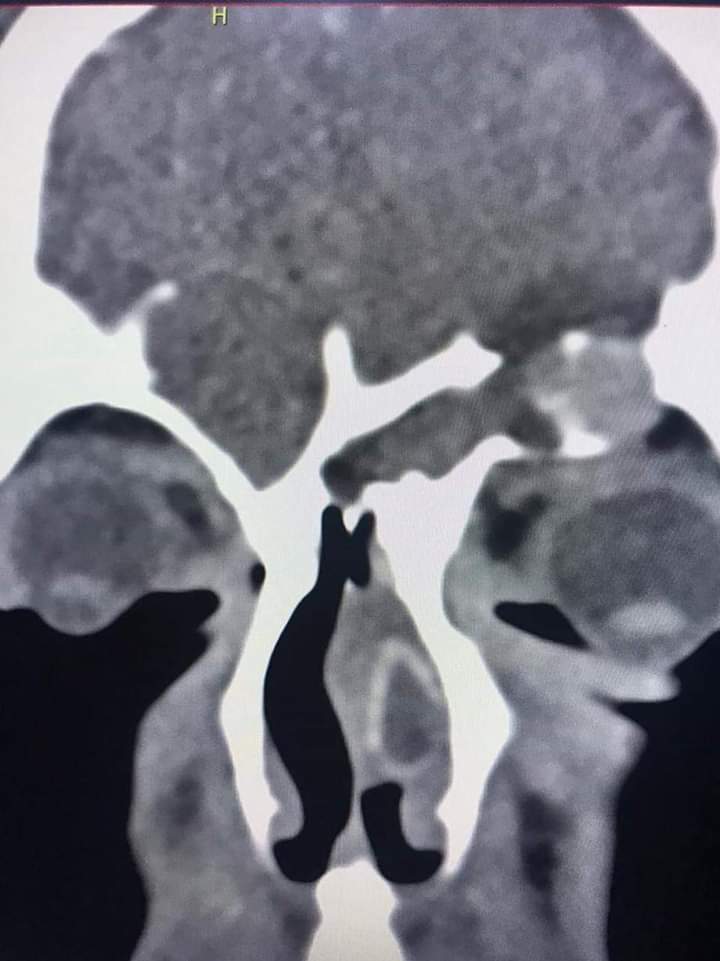

قام فريق طبي من دائرة الأذنية في الخدمات الطبية الملكية برئاسة العقيد الطبيب نبيل الشواقفة مستشار جراحة الأنف وقاع الجمجمة بإجراء عملية تنظير معقدة ونادرة لشاب يبلغ من العمر ٢٠ عاما، يعاني من التهاب فطري حاد ممتد إلى قاع الدماغ وحجرة العين مع وجود ثقب في قاع الجمجمة.

وبين الشواقفة ان المريض عندما راجع عيادة الأنف والأذن والحنجرة في مدينة الحسين الطبية كان يشكو من صداع شديد وانسداد في الأنف وصعوبة في التنفس، وبعد إجراء الفحص السريري والشعاعي تبين وجود إلتهاب حاد ممتد إلى قاع الجمجمة وحجرة العين وثقب في قاع الجمجمة، تقرر على أثرها إجراء العملية التي تعتبر من العمليات النادرة والمعقدة التي تحتاج فريق طبي متخصص .